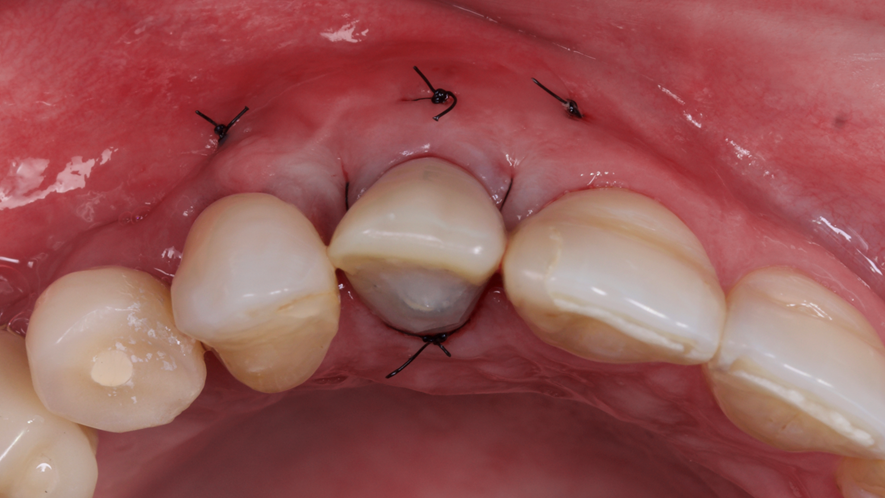

Este trabalho tem como objetivo relatar um caso clínico de exodontia minimamente invasiva de um incisivo lateral superior com fratura radicular, realizando implante imediato em alvéolo pós-extração, enxerto de tecido conjuntivo subepitelial e osso bovino liofilizado para preenchimento de GAP, prontamente à instalação de pilar reto e provisório imediato.